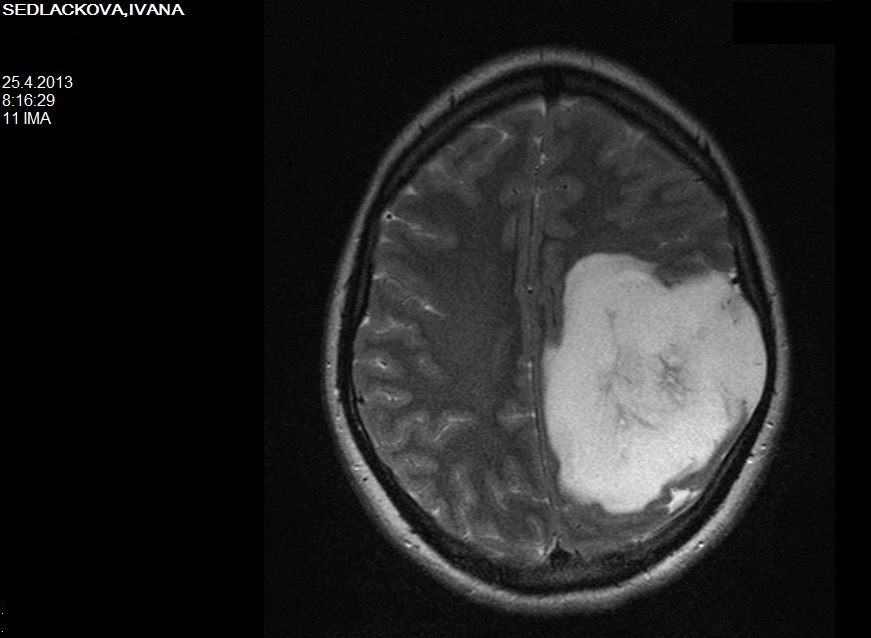

Asi mi to nedocházelo. Fakt jsem chtěla jít domů, dcera měla tehdy horečku. A doktor se mě pak zeptal, jestli jsem viděla snímek z rezonance a ukázal mi, jak můj mozek vypadá. Více jak čtvrtinu zabíral nádor. Až tehdy jsem ztratila důvěru sednout si za volant a někam jet. Tak jsem tam teda zůstala.

Snímek mozku z magnetické rezonance.